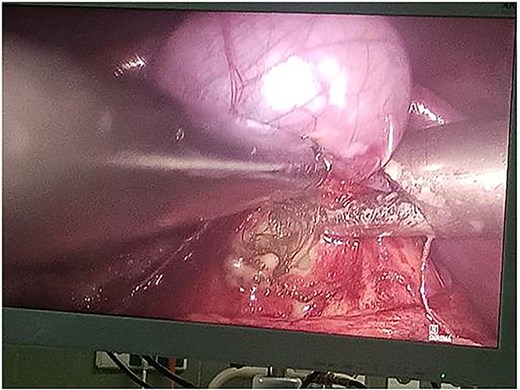

Following multidisciplinary consultation, the lesion was diagnosed as an E. granulosus hydatid cyst. Laparoscopic resection was planned (Fig. 2). Intraoperatively, surgeons suspected the cyst might represent a teratoma. Resection was performed under vascular clamping, with the cutting plane passing through healthy tissue, ensuring complete removal of the cyst wall (Fig. 3). The surgery was uneventful.

Resected specimen of the hepatic cystic mass, removed laparoscopically under vascular clamping. The excision was performed through healthy liver parenchyma, ensuring complete removal of the cyst wall. The gross appearance, featuring heterogeneous soft tissue components and hair-like structures, initially raised suspicion of a hepatic teratoma among the surgical team.